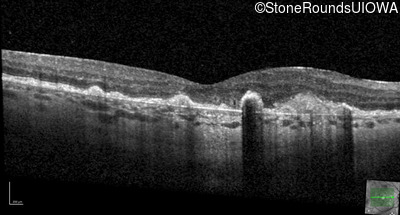

Malattia Leventinese (IIJ)

Malattia Leventinese (IIJ)

This 43 year old woman has experienced a gradual reduction in her central vision for the past 3 years.

| Malattia Leventinese | EFEMP1 | Arg345Trp CGG>TGG | AD |